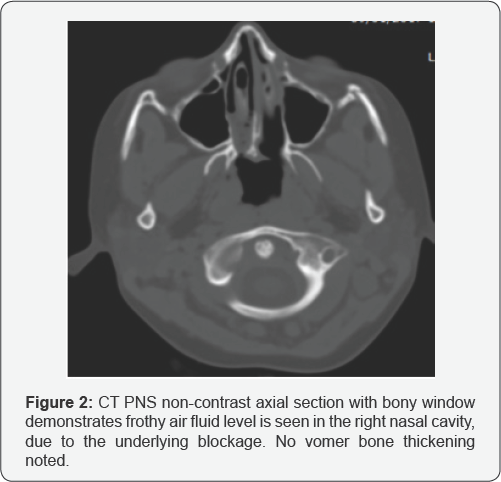

Imaging: CT scan of paranasal sinus was requested (Figures 1 & 2).

Findings of Non-contrast CT scan of PNS

a) Unilateral posterior osseous narrowing at the right posterior nasal cavity with an element of total bony occlusion at the posterior inferior passage of the right nasal cavity

b) Frothy air-fluid level noted opacifying the right nasal cavity.

c) No vomer bone thickening is noted

Diagnosis: Unilateral right sided choanal atresia